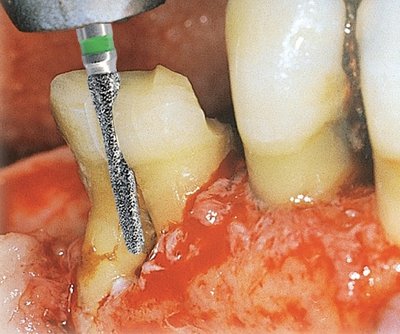

Edenta GSD1 - chirurgické diamantové nástroje, Osteotom - 3 ks